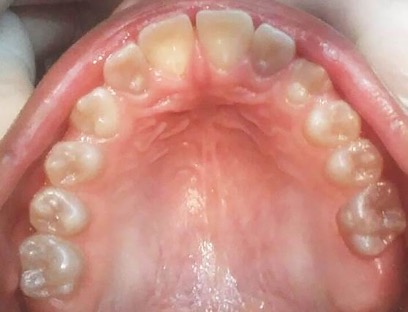

En el año 2010, el mantenedor de espacio fijo superior se descementó, pero debido a la cercana erupción de los incisivos centrales superiores permanentes obser-vada radiográficamente (Figura 5), se decidió no recementarlo, confeccionando coronas de acero independientes en los 4 molares superiores primarios (5.4, 5.5, 6.4 y 6.5) y en el 7.5, previa restauración de las lesiones de caries con ionómero vítreo (Figura 6). Cuando se observó la erupción del 4.1 y 3.1, y de los 4 molares permanentes, se realizaron 3 aplicaciones de barniz de fluoruro de sodio al 5%, cumpliendo con los protocolos establecidos.

Figura 5: Examen clínico intraoral superior, sector anterior y radiografía panorámica año 2010.

Figura 6: Postoperatorias clínicas maxilar superior e inferior año 2010.